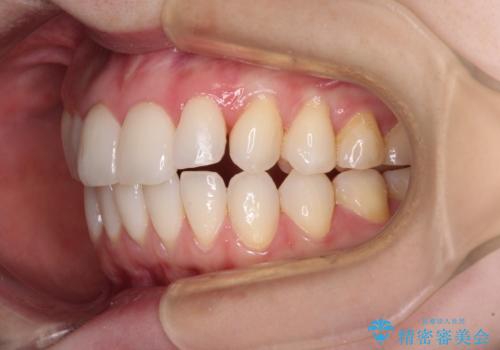

- 前歯のデコボコや八重歯の様になっていることを気にして来院された患者様です。

犬歯捻れて前方に飛び出しており、下顎前歯もそれに沿うようにデコボコとなっていました。

IPR(歯と歯の間を削る処置)によりスペースを獲得して上下顎前歯のデコボコを改善し、前歯が前方に突出しないように設定した上で、インビザラインにて矯正治療を行うこととしました。

途中体調を崩され、長い期間矯正治療を休むことになったため4年半ほどの治療期間がかかりました。